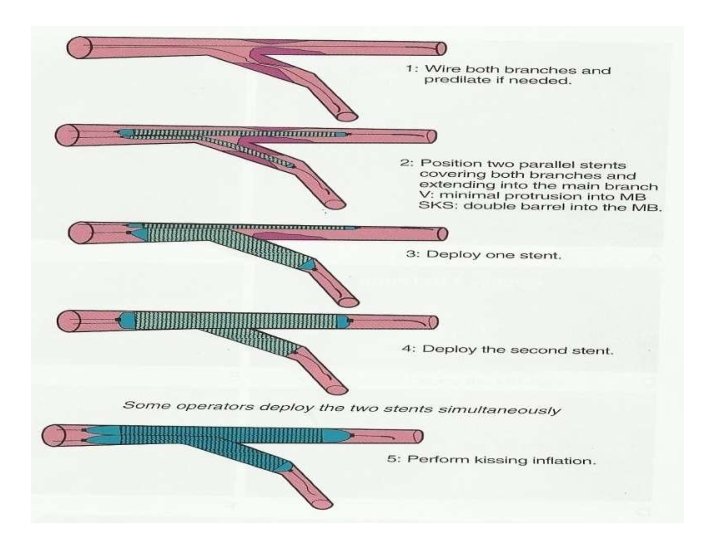

Stenting techniques 1)Provisional • Mainvessel stenting ± side branchangioplasty (Provisional) Tstenting, • TAP, • REVERSEINTERNAL CRUSH • REVERSECULOTTE. 2) elective • Culotte-stenting • Crush technique (reversecrush) T TECHNIQUE AND TAP • V STENTING • Y STENTING(SKS technique)

V technique